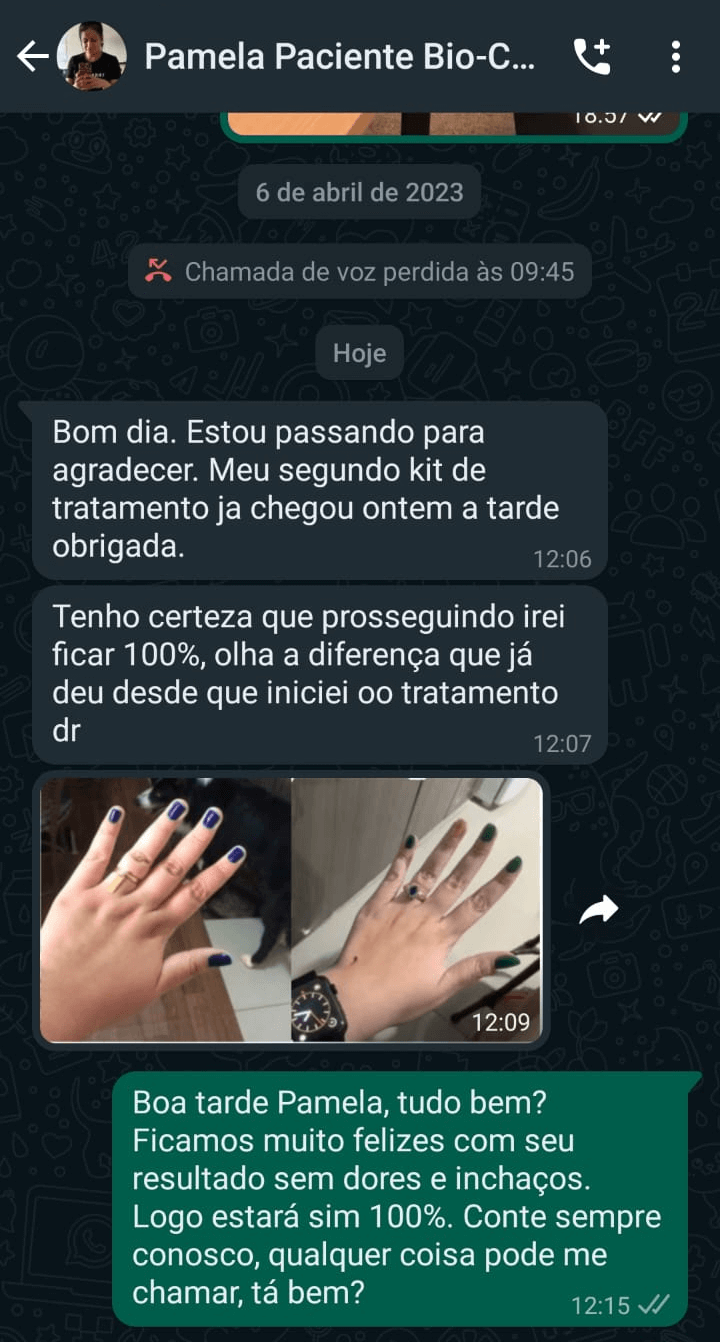

FAÇA PARTE DO NOSSO TIME DE CLIENTES QUE AMARAM

Desafio Bio-Cúrcuma + Magnésio!

Se não houver resultados em 30 dias você pode devolver!

É sério! Você fica satisfeito, ou compramos o Bio-curcúma + Magnésio de volta de você. Se por qualquer motivo achar que o Bio-curcúma + Magnésio não ajudou, nosso compromisso é devolver a quantia paga pelo seu kit de potes de Bio-curcúma + Magnésio.

É recomendando o uso por 3 meses consecutivos para obter os melhores resultados. No entanto, há vários relato de pessoas que já sentem ótimos resultados já nos primeiros dias de uso.